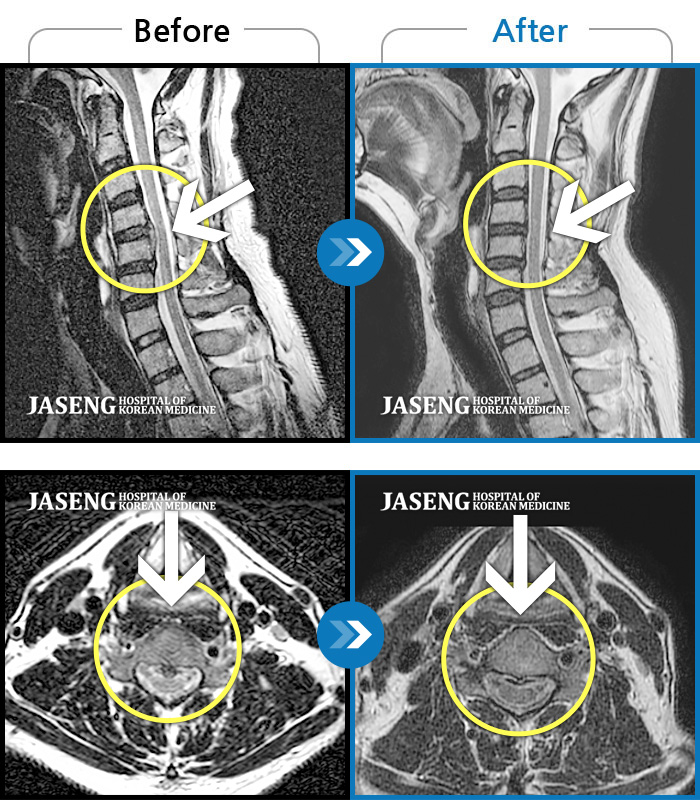

Before

After

"허리디스크 치료하는 동안 예전에 치료 받았던 목디스크도 확인해보고 싶어요”

2019.12.10 ~ 2019.12.10